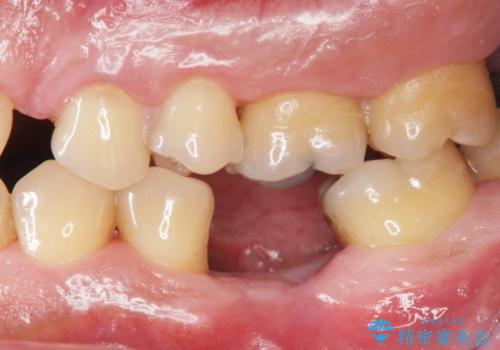

自然な仕上がりと、久しぶりのしっかりと噛める感覚に大変満足いただくことができました。

インプラン治療は、ブリッジと異なり前後の歯を削る必要がなく、入れ歯と違い取り外しの必要がありません。